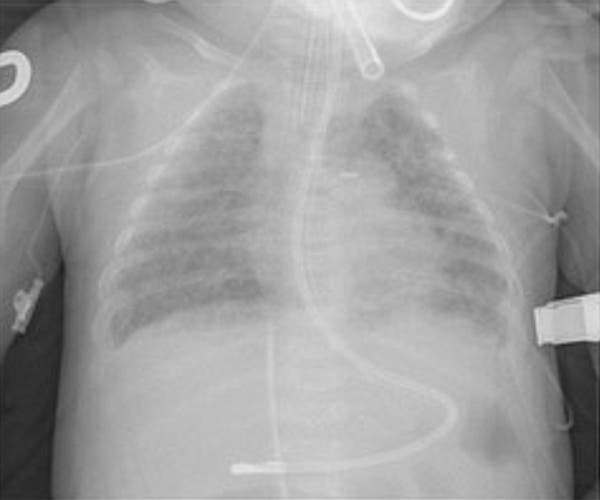

La displasia broncopulmonar (DBP) es una enfermedad pulmonar crónica que, como consecuencia de múltiples factores, añadidos a la inmadurez de la vía aérea, provoca una disminución del crecimiento pulmonar, dando lugar a una limitación en la función respiratoria de grado variable.

Los recién nacidos prematuros, sobre todo los que padecen displasia broncopulmonar, tienen mayor riesgo de presentar episodios de sibilancias de repetición, así como más posibilidades de padecer asma o cualquier obstrucción al flujo aéreo.

La DBP se desarrollará hasta en el 40% de los bebés que nacen antes de las 28 semanas de gestación y en el 60% por debajo de las 26 semanas, tal y como se especifica en el registro GEIDIS.

El 96% de los pacientes de DBP nacieron antes de las 32 semanas de gestación, situándose la edad media en las 27 semanas. El 60,5% son varones y el peso medio fue de 900 gramos. La estancia hospitalaria media fue de tres meses.

«Si después de nacer estos niños, además, padecen algún problema respiratorio agudo, o infecciones, o su nutrición no es la adecuada, o han tenido necesidad de terapias prolongadas, como oxígeno o ventilación mecánica, el caso se agravaría, dando lugar a la insuficiencia respiratoria crónica relacionada con la prematuridad o displasia broncopulmonar; que, a su vez, condicionará aún más al paciente durante la edad adulta», recalca.

El doctor William Northway describió la displasia broncopulmonar en 1967, cuando los niños sobrevivían con pulmones enfisematosos, «rotos»; que reaccionaban con fibrosis o con metaplasia escamosa -neoplasia en la mucosa respiratoria-. Entonces, la DBP provocaba insuficiencia respiratoria muy grave que se relacionaba más con el tratamiento que con la propia prematuridad.

«Ahora, estamos ante una enfermedad nueva; una patología respiratoria que origina pulmones inmaduros, incompetentes; situación que se mantendrá, al menos, hasta que el paciente cumpla los 25 años de edad, fin del periodo de evolución natural de unos pulmones sanos», estima Sánchez Luna.